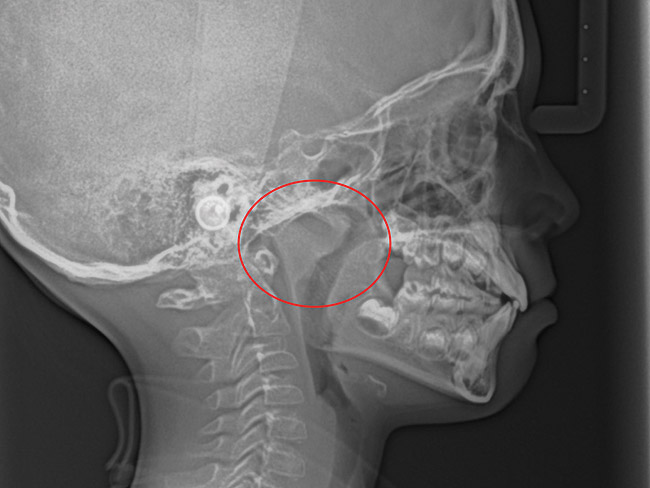

Tonsils and adenoids should be judged against the relative size of the airway rather than the absolute size of the lymphoid tissue46 (Figure 5 and Figure 6). Adenoids are located at the posterior of the nasal cavity on the roof of the nasopharynx (Figure 7). The normal distance from the adenoids to the soft palate for an acceptable airway should be at least 12 mm. For each millimeter decrease, the odds of the child snoring increase 1.61 times. Mouth breathers typically show a smaller upper airway dimension as well.47 The adenoid and tonsillar obstruction creates the trigger, but the deviate facial and neck muscle recruitment and tongue hypotonia cause the maldevelopment.48

(11.) Adenoidal tissue blocking the velopharyngeal airway.

Figure 11